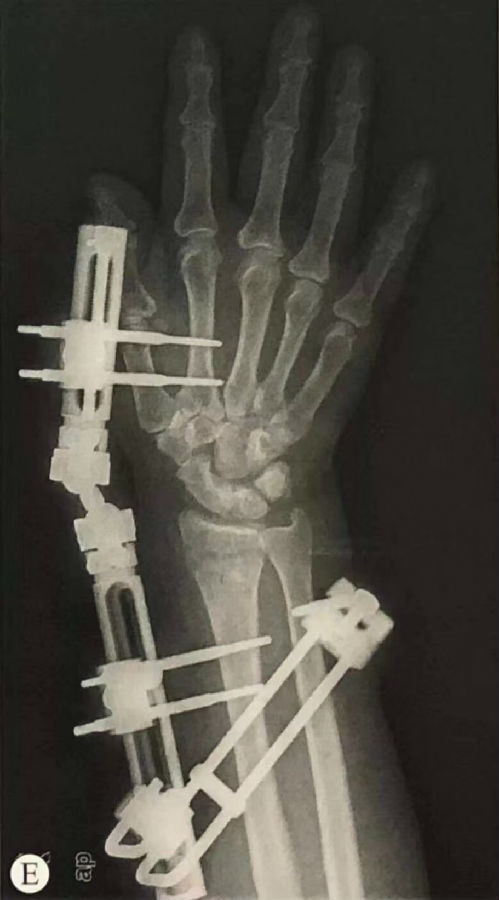

三、手法复位+微型外固定架

石膏固定不能控制粉碎性不稳定骨折复位后再移位以及晚期塌陷,可外固定架治疗,依靠“韧带修复"的生物力学原理使骨折复位,利用软组织在牵引状态下对骨折片的整复能力复位。同时可中和各种导致畸形的力,防止发生再移位。

关键:1是复位,2是固定。

1、先手法复位同前。

2、穿针技术:

复位后在前臂、腕(骨折远端)或掌骨处(第二掌骨)穿针。桡骨茎突近侧10至20cm称之“桡骨裸区”,在桡骨的背侧与掌侧面交界处穿针(在肱桡肌腱背侧穿针)切口3-5cm防止伤及神经肌腱。第二掌骨在其桡侧面穿针,穿过二掌骨及三掌骨桡侧骨皮质。

维持复位的情况下,连接外固定支架,将外固定架旋转中心同腕关节旋转中心置于同一轴线上。

图6 正侧位透视,检查桡骨长度、掌倾角和尺偏角是否恢复,调整固定角度直至骨折复位满意